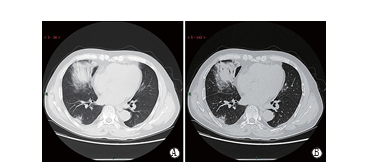

1.2 患者在我院诊疗经过概述

入院后予以抗病毒治疗,予以传统氧疗进行呼吸支持,但病情呈进展趋 势。入院第3天,患者出现呼吸困难及憋喘症状加重,伴血氧饱和度下降至65%,呼吸频率在40次/min以 上,无创通气1 h无改善,指脉氧维持在80%~85%,血气分析SpO2 56%、PCO2 61 mmHg,然后行气管插管 连接呼吸机辅助通气,复查CT(图1)提示:双肺病变斑片明显增大并出现双肺部大部分实变,俯卧位通气等复查CT明显进展,遂气管插管行有创机械通气,采取肺保护性通气策略,联合俯卧位通气但效果仍不明显,出现二氧化碳蓄积(PaCO2 75 mmHg)。

图1 患者肺部CT影像学变化

A. 2020年1月5日;B. 1月7日;C. 1月21日

VV-ECMO运行(图2)后,ECMO管理团队进行常规抗凝、氧流量、血流量、血氧(膜前、膜后)等监测,逐步降低ECMO支持氧浓度,每日复查床边胸片,5 d后关闭ECMO氧流,观察6 h,评估撤机指征,患者氧合可维持正常,予以拔管撤机。呼吸机维持治疗,次日评估呼吸机参数后,行呼吸机撤机试验,拔除气管插管,患者神志清醒,后逐步下床活动无障碍,鼻导管吸氧氧流量维持在2~3 L,氧合维持正常,至第7天成功撤离ECMO,第8天清醒后撤离呼吸机,第12天转出ICU,转入感染科继续隔离观察,复查新型冠状病毒(2019-nCoV)核酸2次阴性,第20天考虑治愈予以出院。